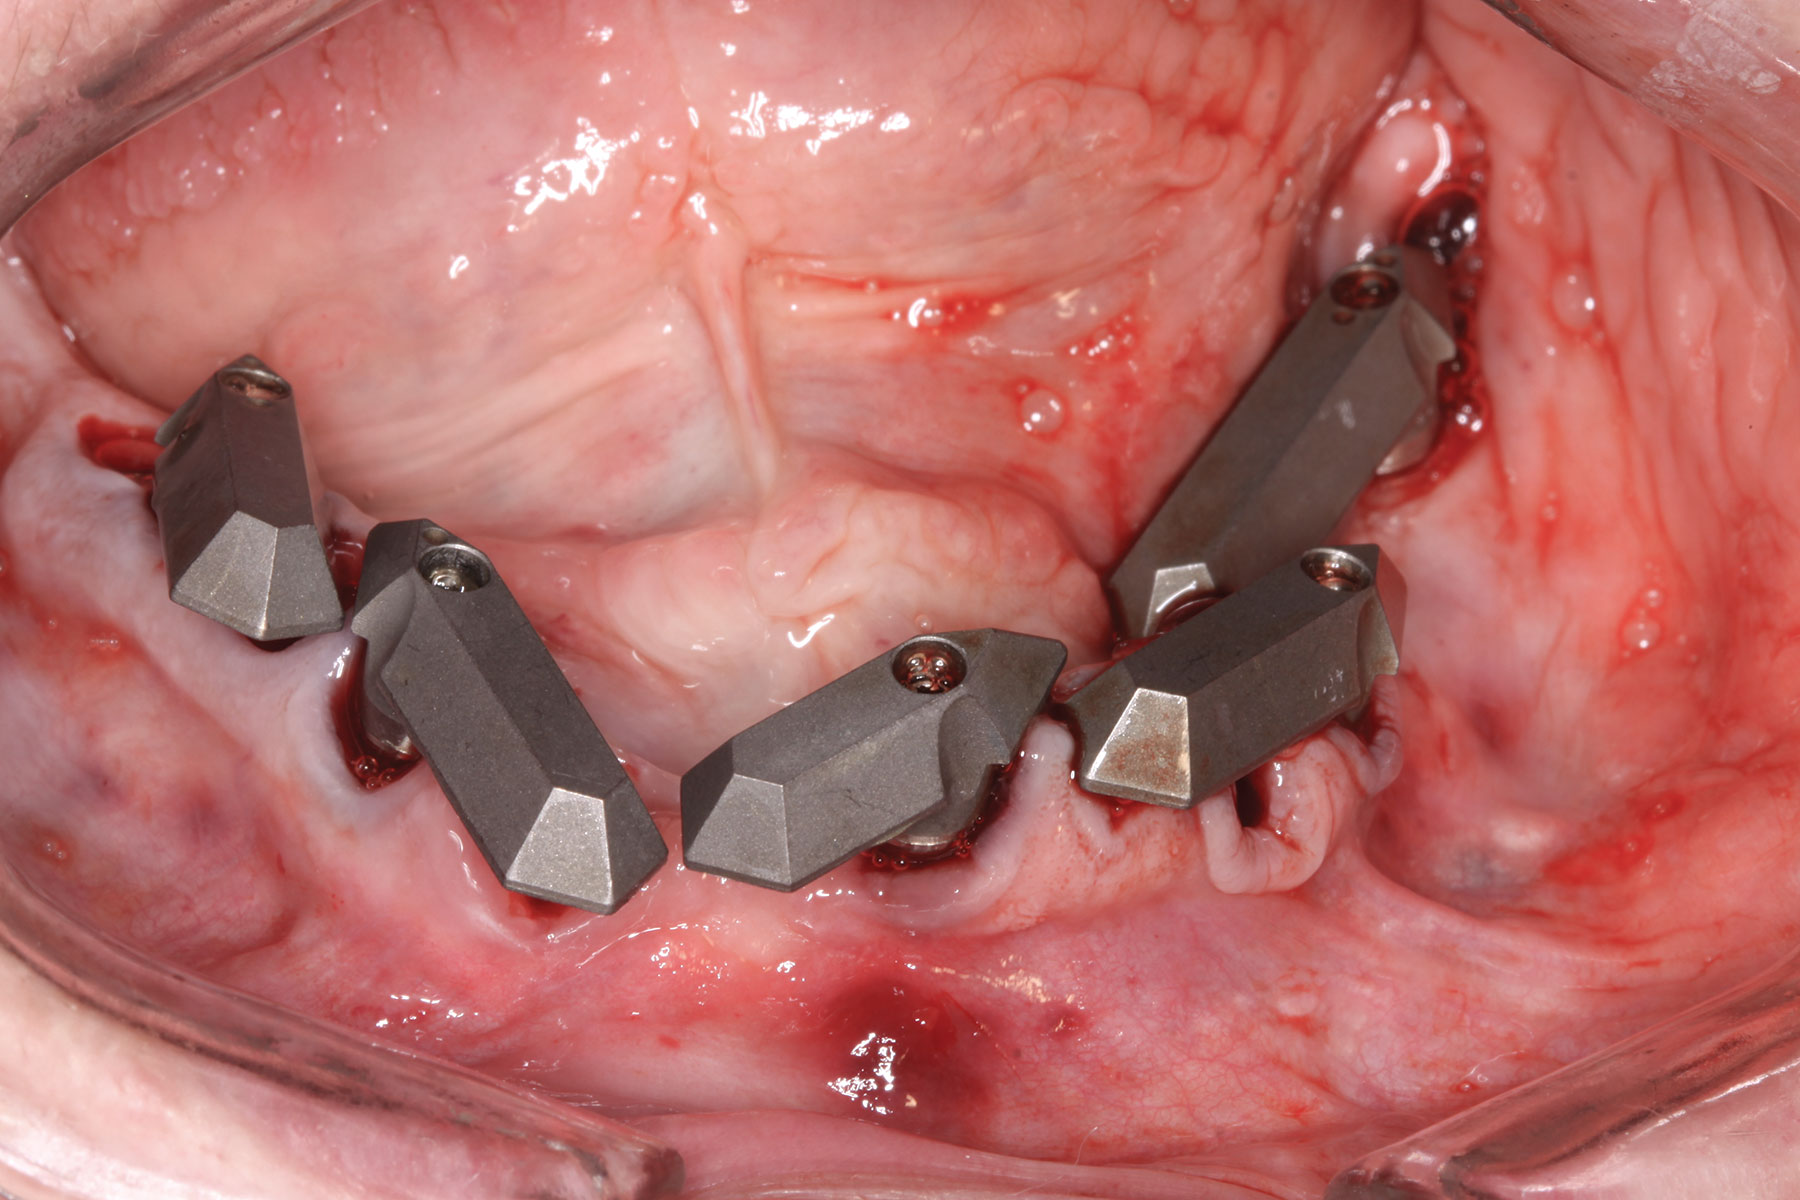

Case 3

A 67-year-old female patient presented with a highly compromised maxillary and mandibular dentition, including teeth Nos. 2 through 15, 17, 21 through 24, and 27 through 30. Soft tissues were of normal contour, and bone profiles were generally sustained and favorable. The patient was excited about the prospect of transforming both her maxillary and mandibular compromised esthetics and function in one visit. (Case 3 is depicted in Figure 23 through Figure 42.)

At the next visit, the patient was anesthetized with xylocaine with 1:100,000 epinephrine. Teeth Nos. 22, 27, and 28 were retained and all other mandibular teeth were extracted. Immediate implants were placed in prosthetically correct positions and multi-unit abutments were torqued to 30 Ncm. This was followed by insertion of screw-retained scan gauges in positions Nos. 18, 24, and 30.

At the completion of surgery for the mandibular arch, teeth Nos. 17, 21 through 24, and 27 through 30 had been carefully extracted. Immediate implants with multi-unit abutments were placed in sites Nos. 21, 24, 28, and 30, and an additional implant with a multi-unit abutment was placed in site No. 18. All multi-unit abutments were torqued to 30 Ncm. In the maxillary arch, at the completion of surgery, teeth Nos. 2 through 15 had been carefully extracted. Immediate implants with multi-unit abutments were placed in sites Nos. 4, 6, 8, 11, and 13, and all multi-unit abutments were torqued to 30 Ncm.

Fig 29. Mandibular flapless immediate implant surgery completed and multi-unit abutments secured to implants.

Figure 29

Fig 30. All mandibular scan gauges in place.

Figure 30